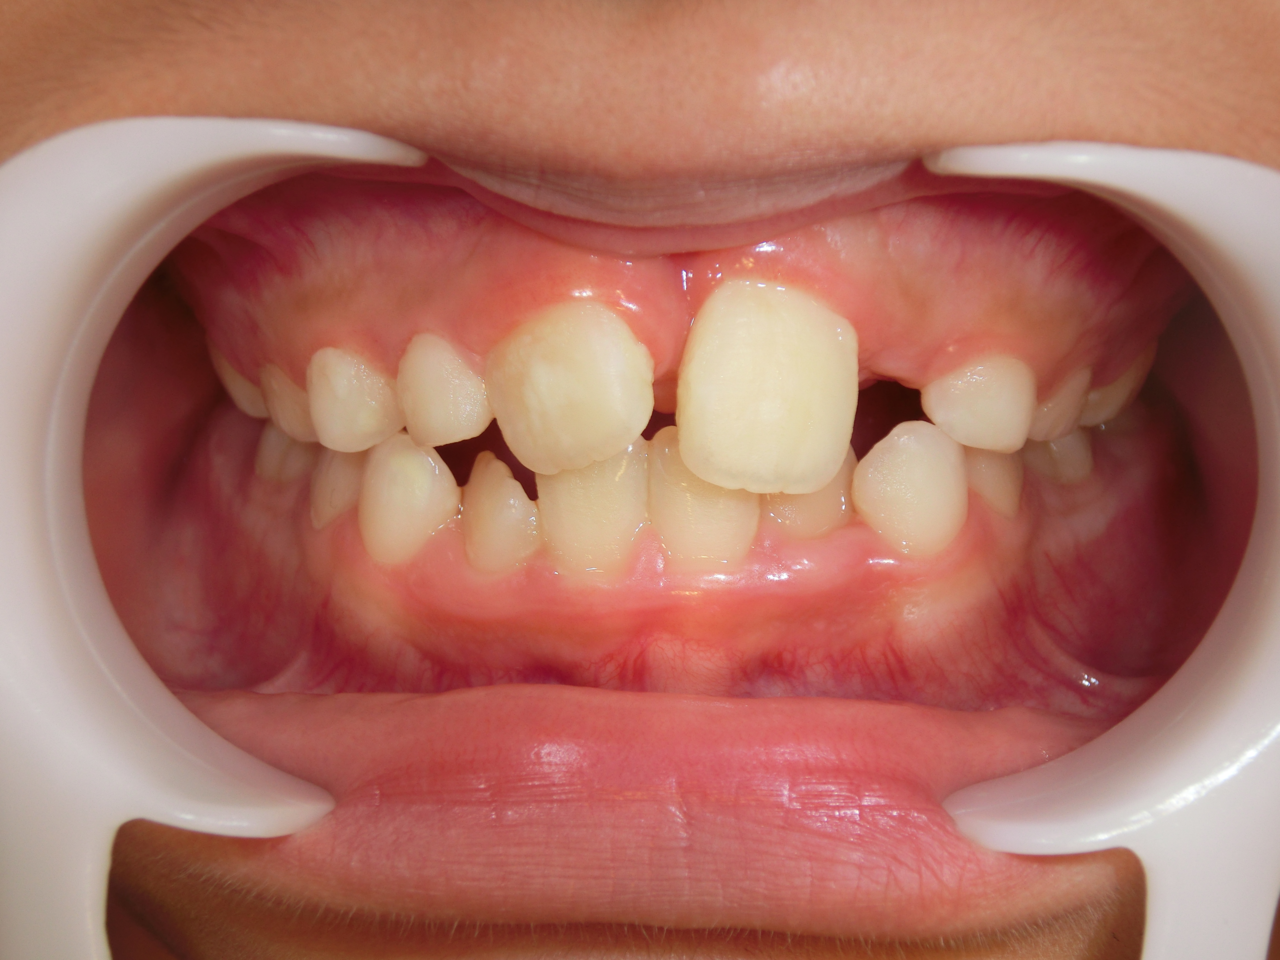

治療前

治療説明 歯科矯正で取り外し可能な矯正方法である床矯正で治療しました

治療期間 2年1か月

治療費200000 円

治療後

治療の副作用(リスク)歯の動き方には個人差があり、予想された治療期間が延長する可能性があります。。床矯正の使用状況、矯正歯科治療には患者さんの協力が必要であり、それらが治療結果や治療期間に影響します。2次矯正が必要になる場合もあります。